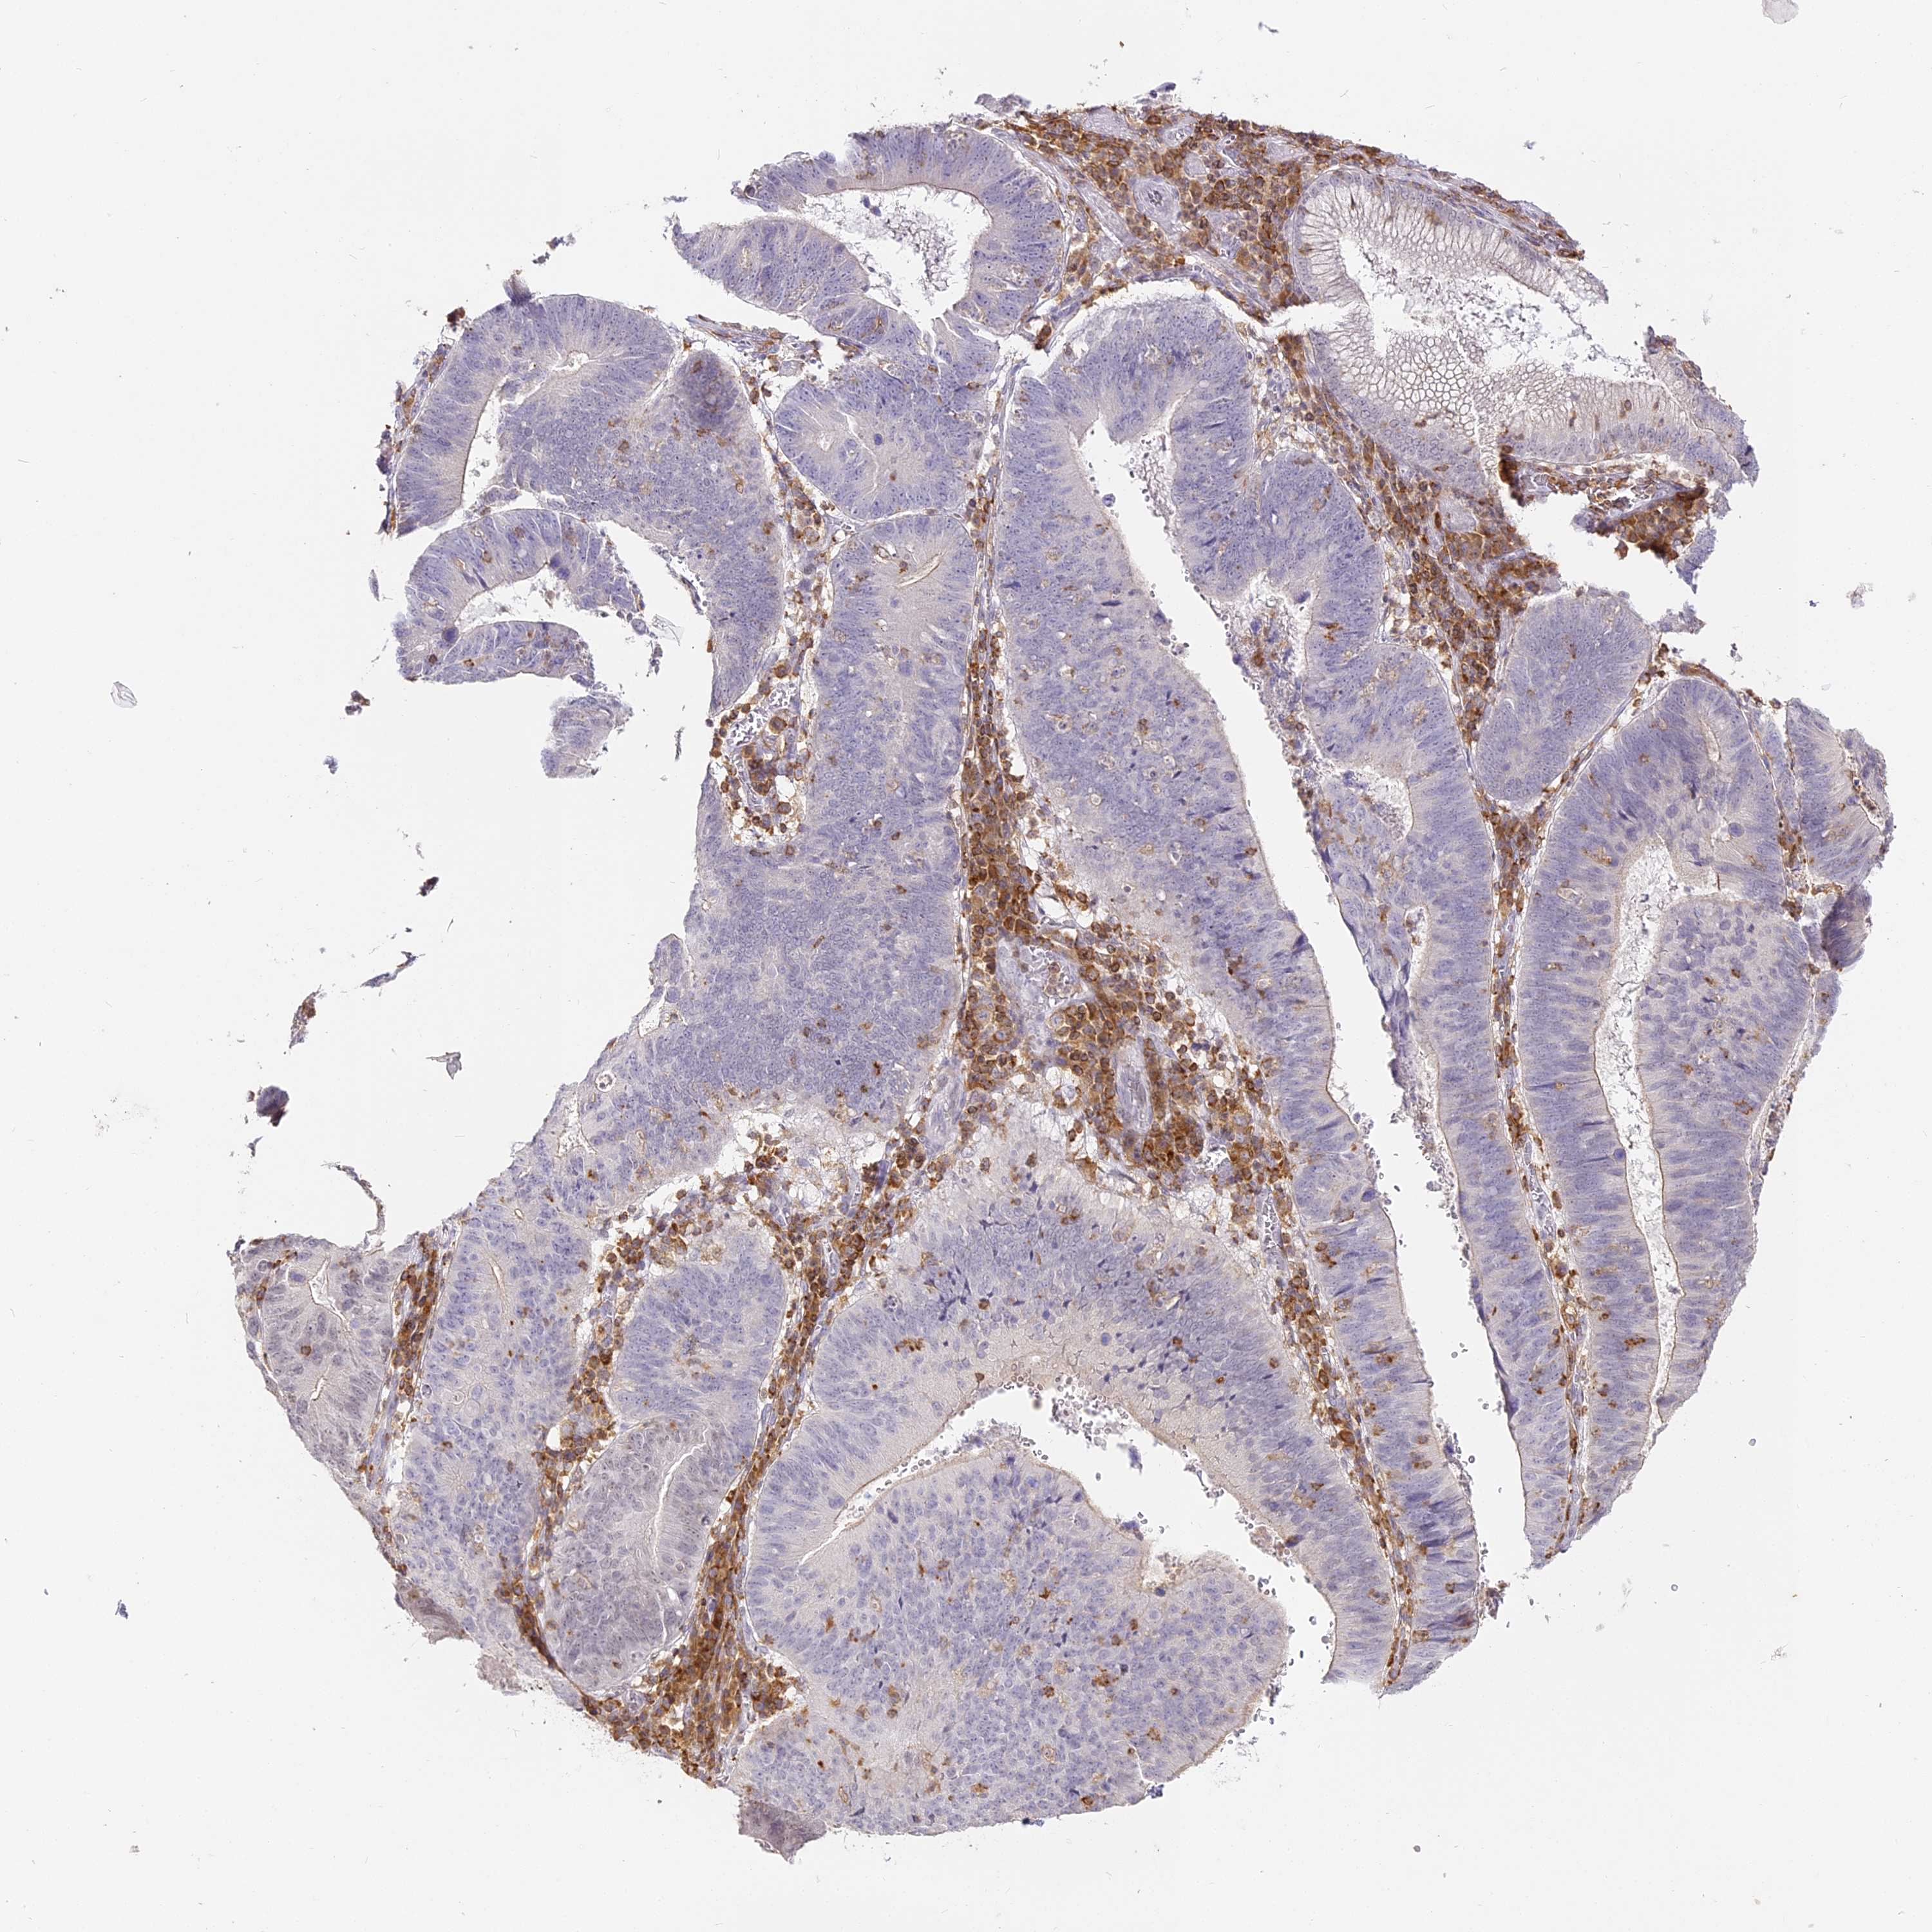

STOMACH CANCER - Protein expressioni

A mouse-over function shows sample information and annotation data. Click on an image to view it in a full screen mode. Samples can be filtered based on level of antibody staining by selecting one or several of the following categories: high, medium, low and not detected. The assay and annotation is described here.

Note that samples used for immunohistochemistry by the Human Protein Atlas do not correspond to samples in the TCGA dataset.

Antibody stainingi

Antibody staining in the annotated cell types in the current human tissue is reported as not detected, low, medium, or high, based on conventional immunohistochemistry profiling in selected tissues. This score is based on the combination of the staining intensity and fraction of stained cells.

Each image is clickable and will lead to virtual microscopy that enables deeper exploration of all samples and also displays staining intensity scores, fraction scores and subcellular localization as well as patient and tissue information for each sample.

Antibody HPA036469

Staining

High

Medium

Low

Not detected

Intensity

Strong

Moderate

Weak

Negative

Quantity

>75%

75%-25%

<25%

None

Location

Nuclear

Cytoplasmic/membranous

Cytoplasmic/membranous,nuclear

Adenocarcinoma, NOS